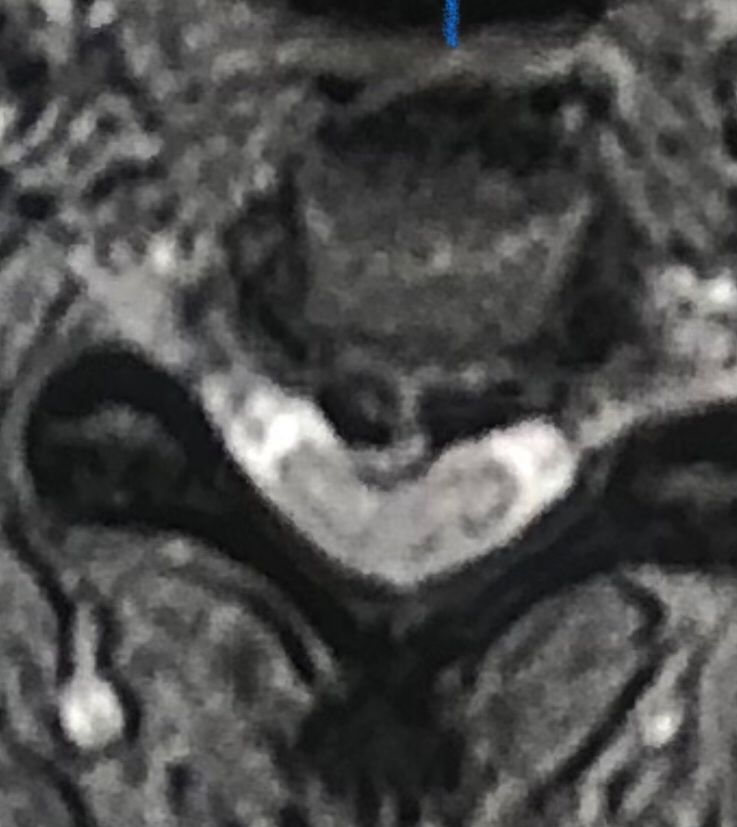

41 years old man presented to my clinic in October 2023 with acute and sever R neck pain with radicular pain to his R upper extremity along C6 dematom since 2 weeks ago. Examination didn’t show any upper motor signs. Was suggested urgent surgery

I ordered EMG/ NCV : showed mild R C6, C7 irritation without any active axonal loss

In his MRI was reported R. para R. IVF Massive extrusion. I decided to control his pain and manage this patient with reevaluation of patient every other session. For 5 sessions i just used acupuncture and laser and IFC and mild adjustments to his R. T3-T7 and mild arthosteem to above and below involved segment. Cervical adjustment considered contraindicated for this patient. From session 6th- 8th i started to use mild/gentle cervical decompression. He used soft cervical collar all the time. His pain decreased by 80 percent

I gave him cervical traction pump to be used 3-5 times per day at home for the next 3 months and i released the patient. He was evaluated every week once for one month and after that every 2 weeks. After 3 month I repeated MRI. Size of the herniated disc was reduced greater than 50 percent. Asked him to do another mri in 6 months

MRIs before and after proper management of this patient: